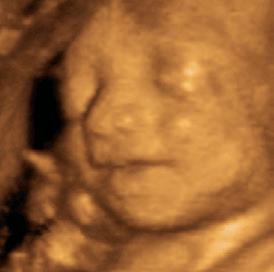

3rd Month: 9–12 Weeks

Unique fingerprints are evident and never change.9 The baby now sleeps, awakens, and exercises her muscles. The baby is very active. The gender can be visually determined and family resemblances may appear.10 At the end of the first trimester, all the organs and systems of her body are functioning.11